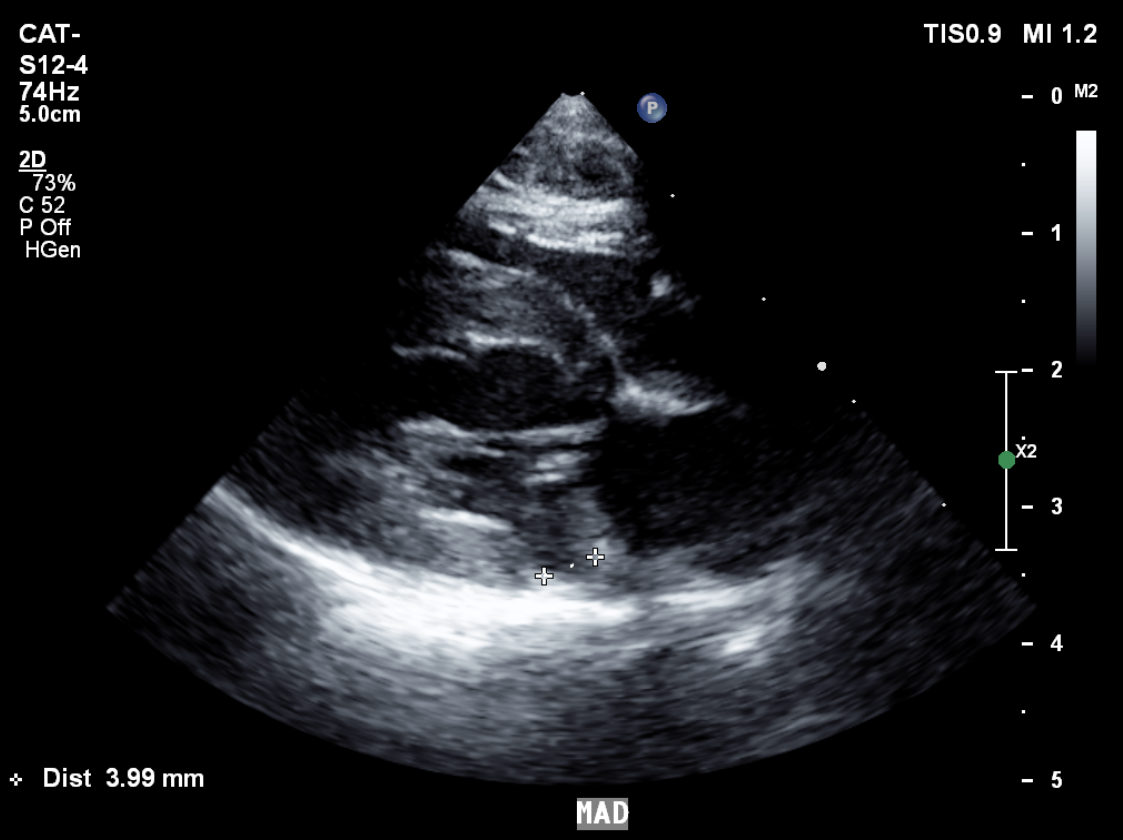

고양이 MAD(mitral annular disjuction) 실 증례

12yr, castrated male pertian cat

low grade HCM and arrythmia

grade 1 LVDD